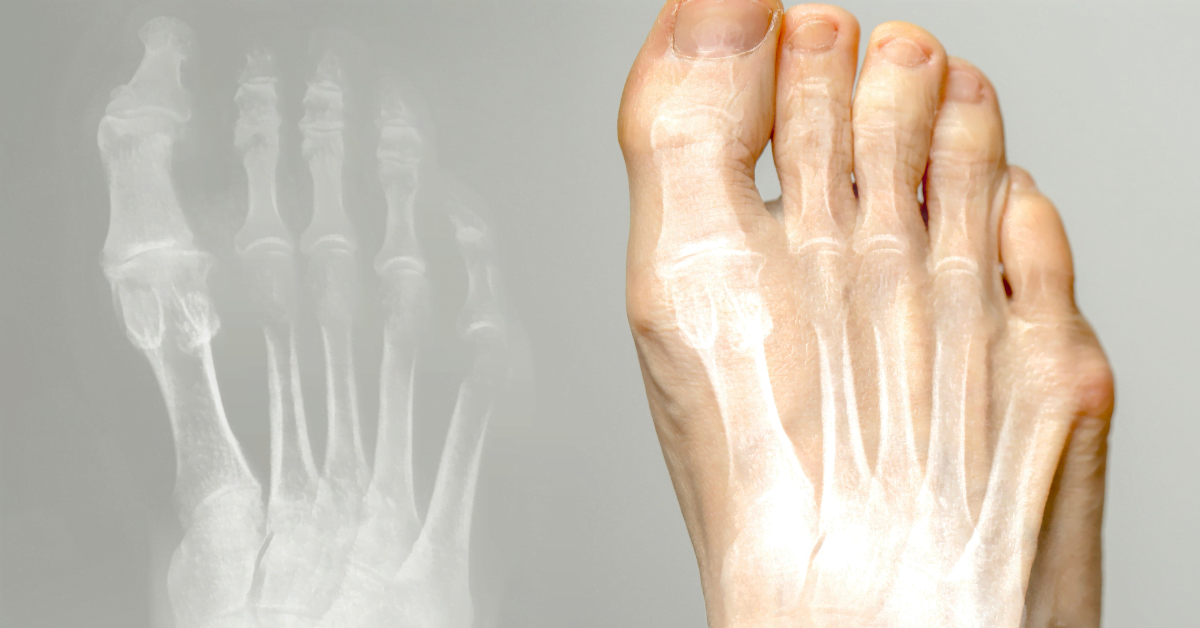

Hallux valgus (knöl tå) är ett tillstånd där stortån pekar inåt och bildar en knöl vid basen. Det kan orsaka smärta och obehag. Här kan du läsa om orsaker, behandling och förebyggande.

Hallux valgus är en snedställning av stortån inåt, med en knöl vid basen. Ofta orsakat av smala skor, höga klackar eller ärftlighet. Kan orsaka smärta och bursit.

Stortån böjer sig mot de andra tårna, vilket skapar en fotknöl. Orsaker: smala skor, högklackat, ärftlighet, plattfot eller artrit. Dåliga skor orsakar tryck och friktion, vilket kan leda till bursit.